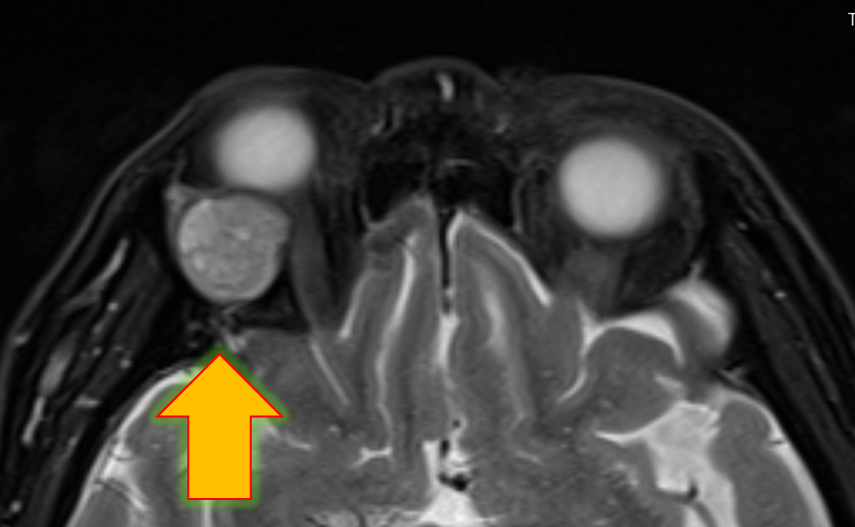

MRI

眼球より後方に眼球内容と同じくらいの信号強度の腫瘍が存在します。